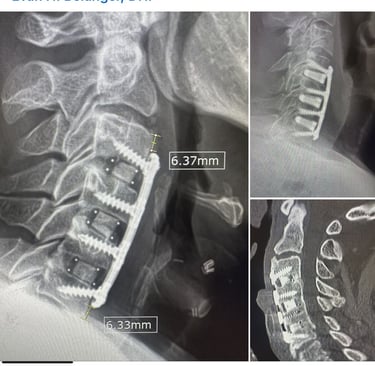

Case #3: ACDF Print

This is a PETG translucent print for a past ACDF surgery, and I wanted to print out real-life, slightly larger parameters to explore the importance of them in surgeries. In this LinkedIn post, surgeons commented on slightly larger parameters for plates being of interest in ACDF cases. In this back-tested case, I found that a slight increase in depth and size leads to slightly stronger plates (due to bending moment) by validating my print via compression and ultimately better use of screws with inserters (insertion).

As this example and previous ones demonstrate, in each of my prints, I have been using parameters (either public or user-defined) to mimic real-life conditions. The next step for me is to incorporate metallic injections (utilizing injection molding). These prints provide a good foundation for this approach, and the mold angle and cavity sizes are the next steps in my career when it comes to product development in this space. Below are the anatomical regions I have also printed to give me reference to validate anatomical fit when working on cases in my free time.